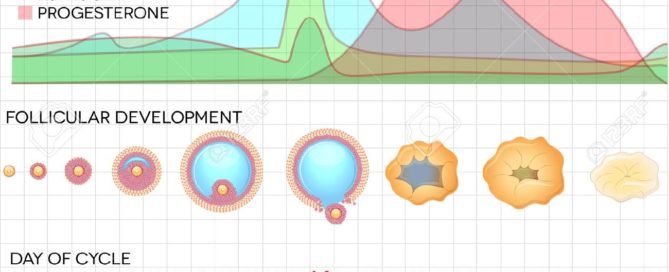

CÓMO UTILIZAR LOS TEST DE OVULACIÓN

CÓMO UTILIZAR LOS TEST DE OVULACIÓN Los test de ovulación [...]